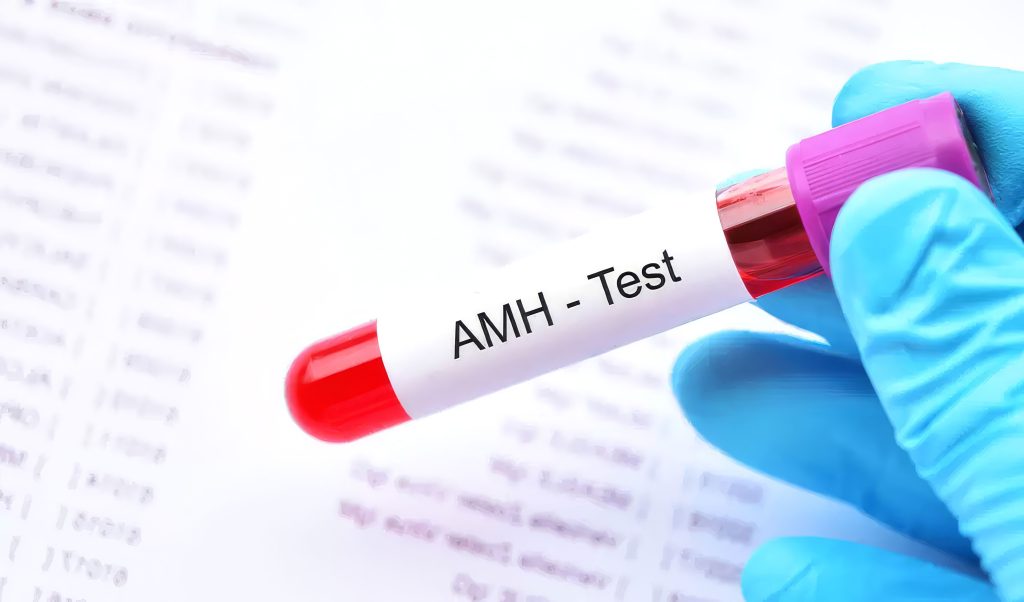

One of the most important factors affecting IVF success is a woman’s ovarian reserve.One of the most reliable ways to evaluate this reserve is through the AMH test.AMH (Anti-Müllerian Hormone)…